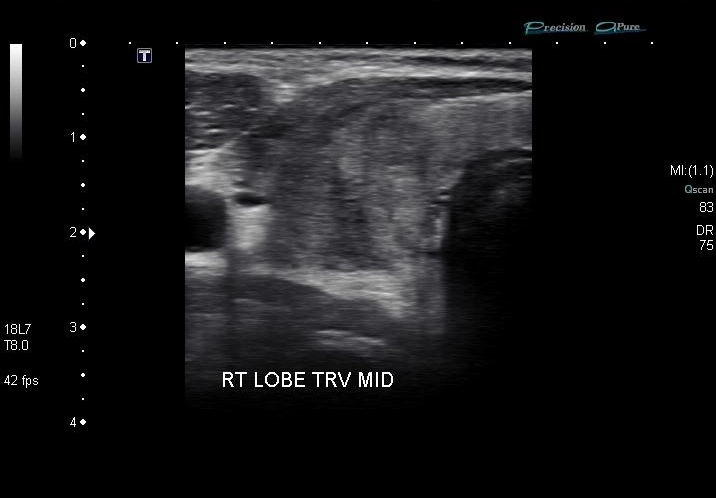

Bệnh Basedow (Graves disease)

Viêm tuyến giáp bán cấp De Quervain (De Quervain thyroiditis)

Viêm tuyến giáp Hashimoto (Hashimoto thyroiditis)